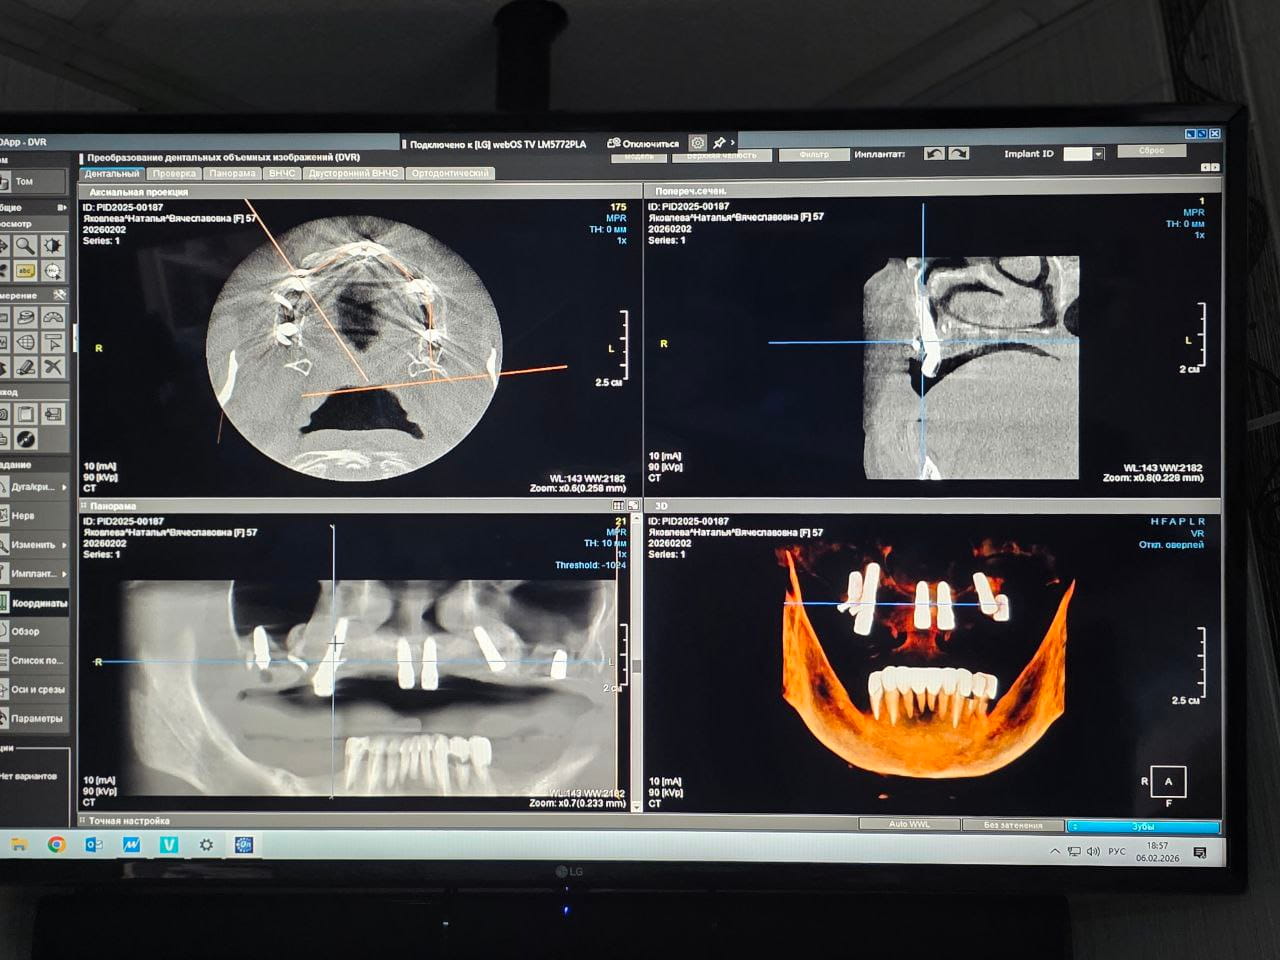

Высокотехнологичный метод диагностики, использующий рентгеновское излучение и цифровую обработку изображений для получения трёхмерных реконструкций зубочелюстной системы.

Томограф создает детальные снимки внутренней структуры зубов, костей и прилегающих тканей, что позволяет выявить патологии, спланировать лечение и повысить точность проводимой терапии.